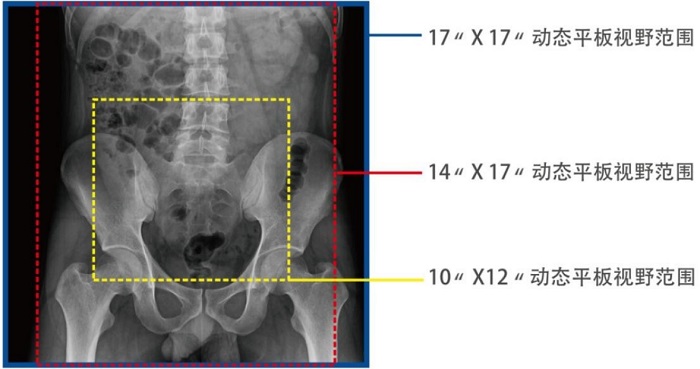

動態(tài)DRF在肛腸科檢查中優(yōu)勢明顯。首先,17×17英寸大幅面成像,對于食道、胃、腸、結腸等大范圍成像部位,可一次曝光完成,極大減少了患者的輻射劑量和檢查時間,且空間分辨率高,與傳統(tǒng)胃腸機相比,圖像質量大幅提升。